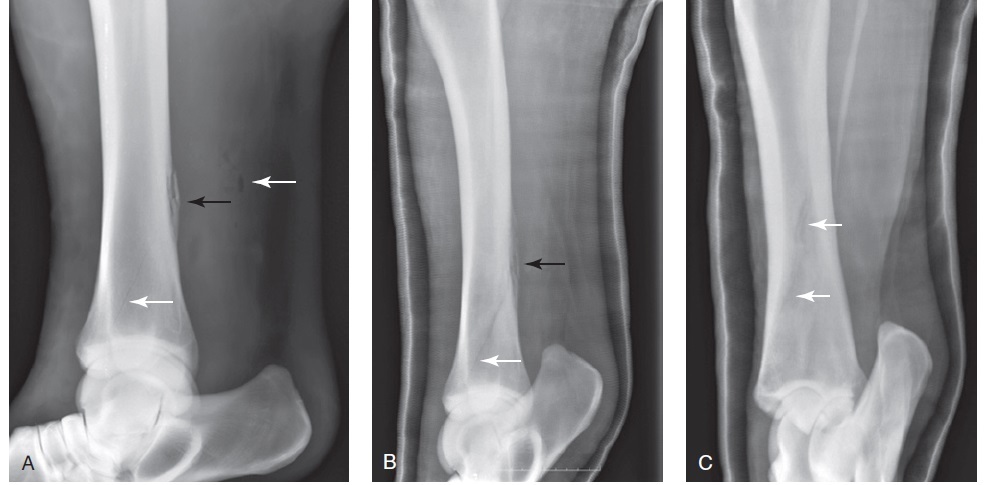

Figure 100-1. A craniolateral–caudomedial oblique radiographic view of the tibia showing the periosteal and endosteal callus (arrow) that accompanies a caudolateral tibial stress fracture.

Figure 100-3. A craniolateral–caudomedial oblique radiographic view of the proximal tibia, which shows a chronic stress fracture of the proximal caudal tibia with associated callus (arrow).